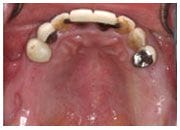

治療前

植入植體